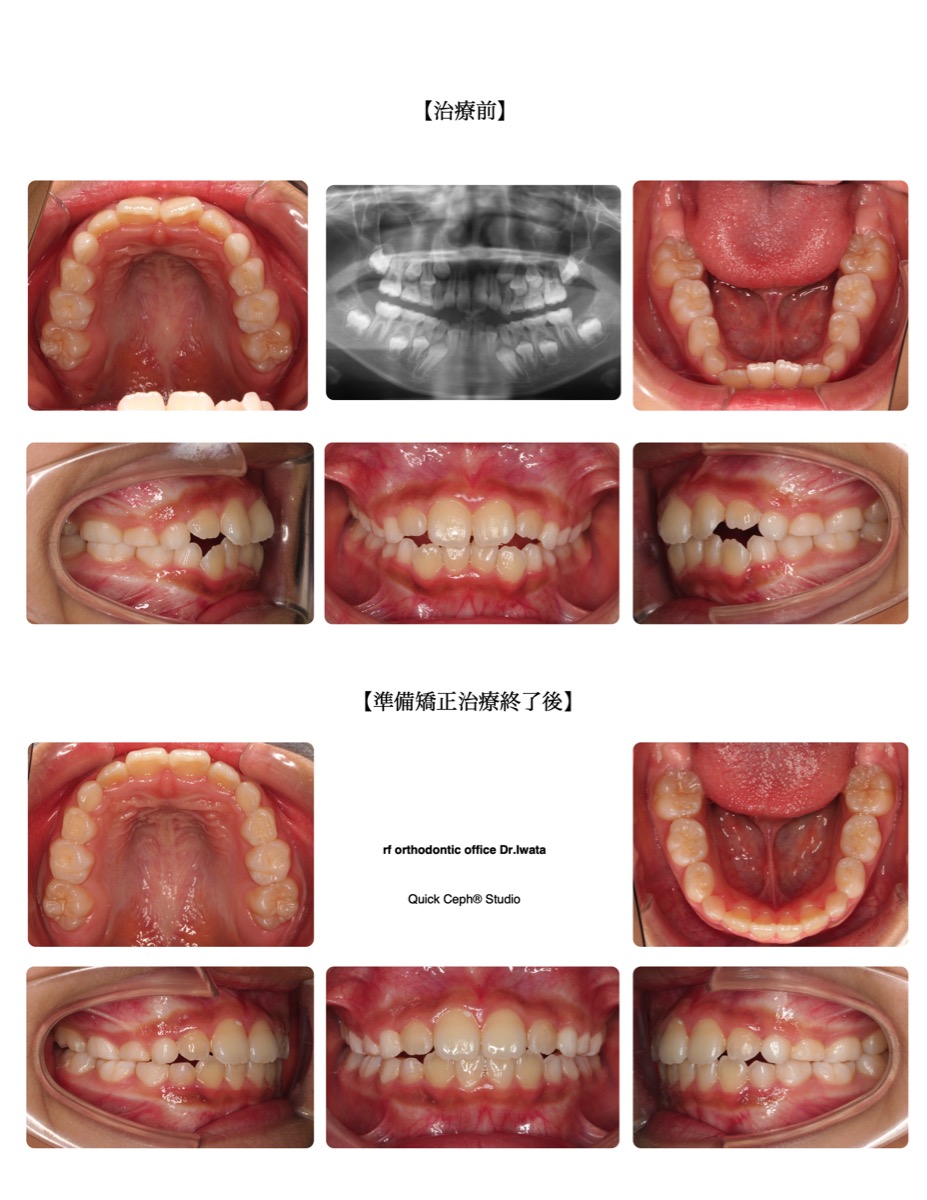

過盖咬合症例 <下顎前歯の先天欠損と上顎前歯の舌側傾斜を併う過蓋咬合に対する非抜歯矯正治療>

【主訴】 上の歯が内向きに生えていて、かみ合わせが深いのが気になる。下の前歯がデコボコしている。【主な症状】…